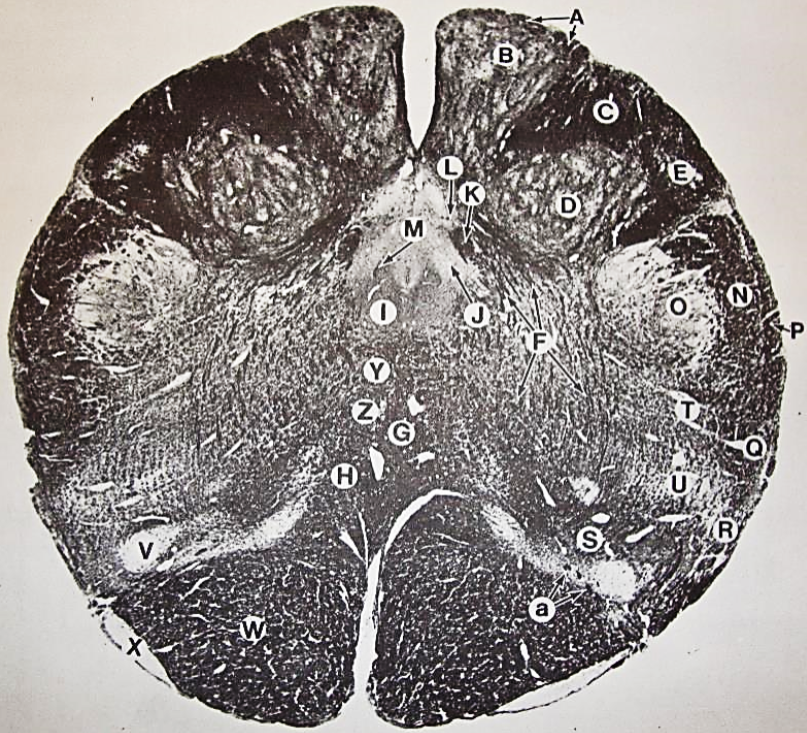

A

Lateral Cuneate nucleus

B

dorsal external arcuate fibers

C + D collectively

vestibular nuclei

C + D collectively

vestibular nuclei

E

dorsal motor nucleus of vagus nerve

F

solitary fasciculus

G

solitary nucleus

H

nucleus ambiguous

I

fascicles of glossopharyngeal nerve

J

hypoglossal nucleus

K

fascicles of hypoglossal nerve

L

dorsal longitudinal fasciculus

M

central tegmental tract

N

inferior olivary nucleus

R

inferior cerebellar peduncle

S

spinal trigeminal tract

T

spinal trigeminal nucleus

U

ventral trigeminothalamic tract

V

pyramidal (corticospinal) tract

W

rubrospinal tract

X

anterior spinocerebellar tract

Y

spinal lemniscus

Z

medial longitudinal fasciculus

a

tectospinal tract

b

medial lemniscus

c

vagus nerve

d

inferior salivatory nucleus